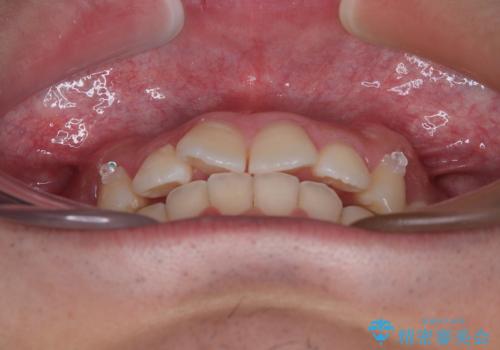

インビザラインによる矯正治療をご希望でしたが、上顎歯列の前方位と鋏状咬合を確実に改善することを目的として、補助装置を併用することとしました。

補助装置を併用せずに治療を終える可能性はありましたが、確実に結果を得るために補助装置を活用しました。

イメージしたとおりの仕上がりとなりました。